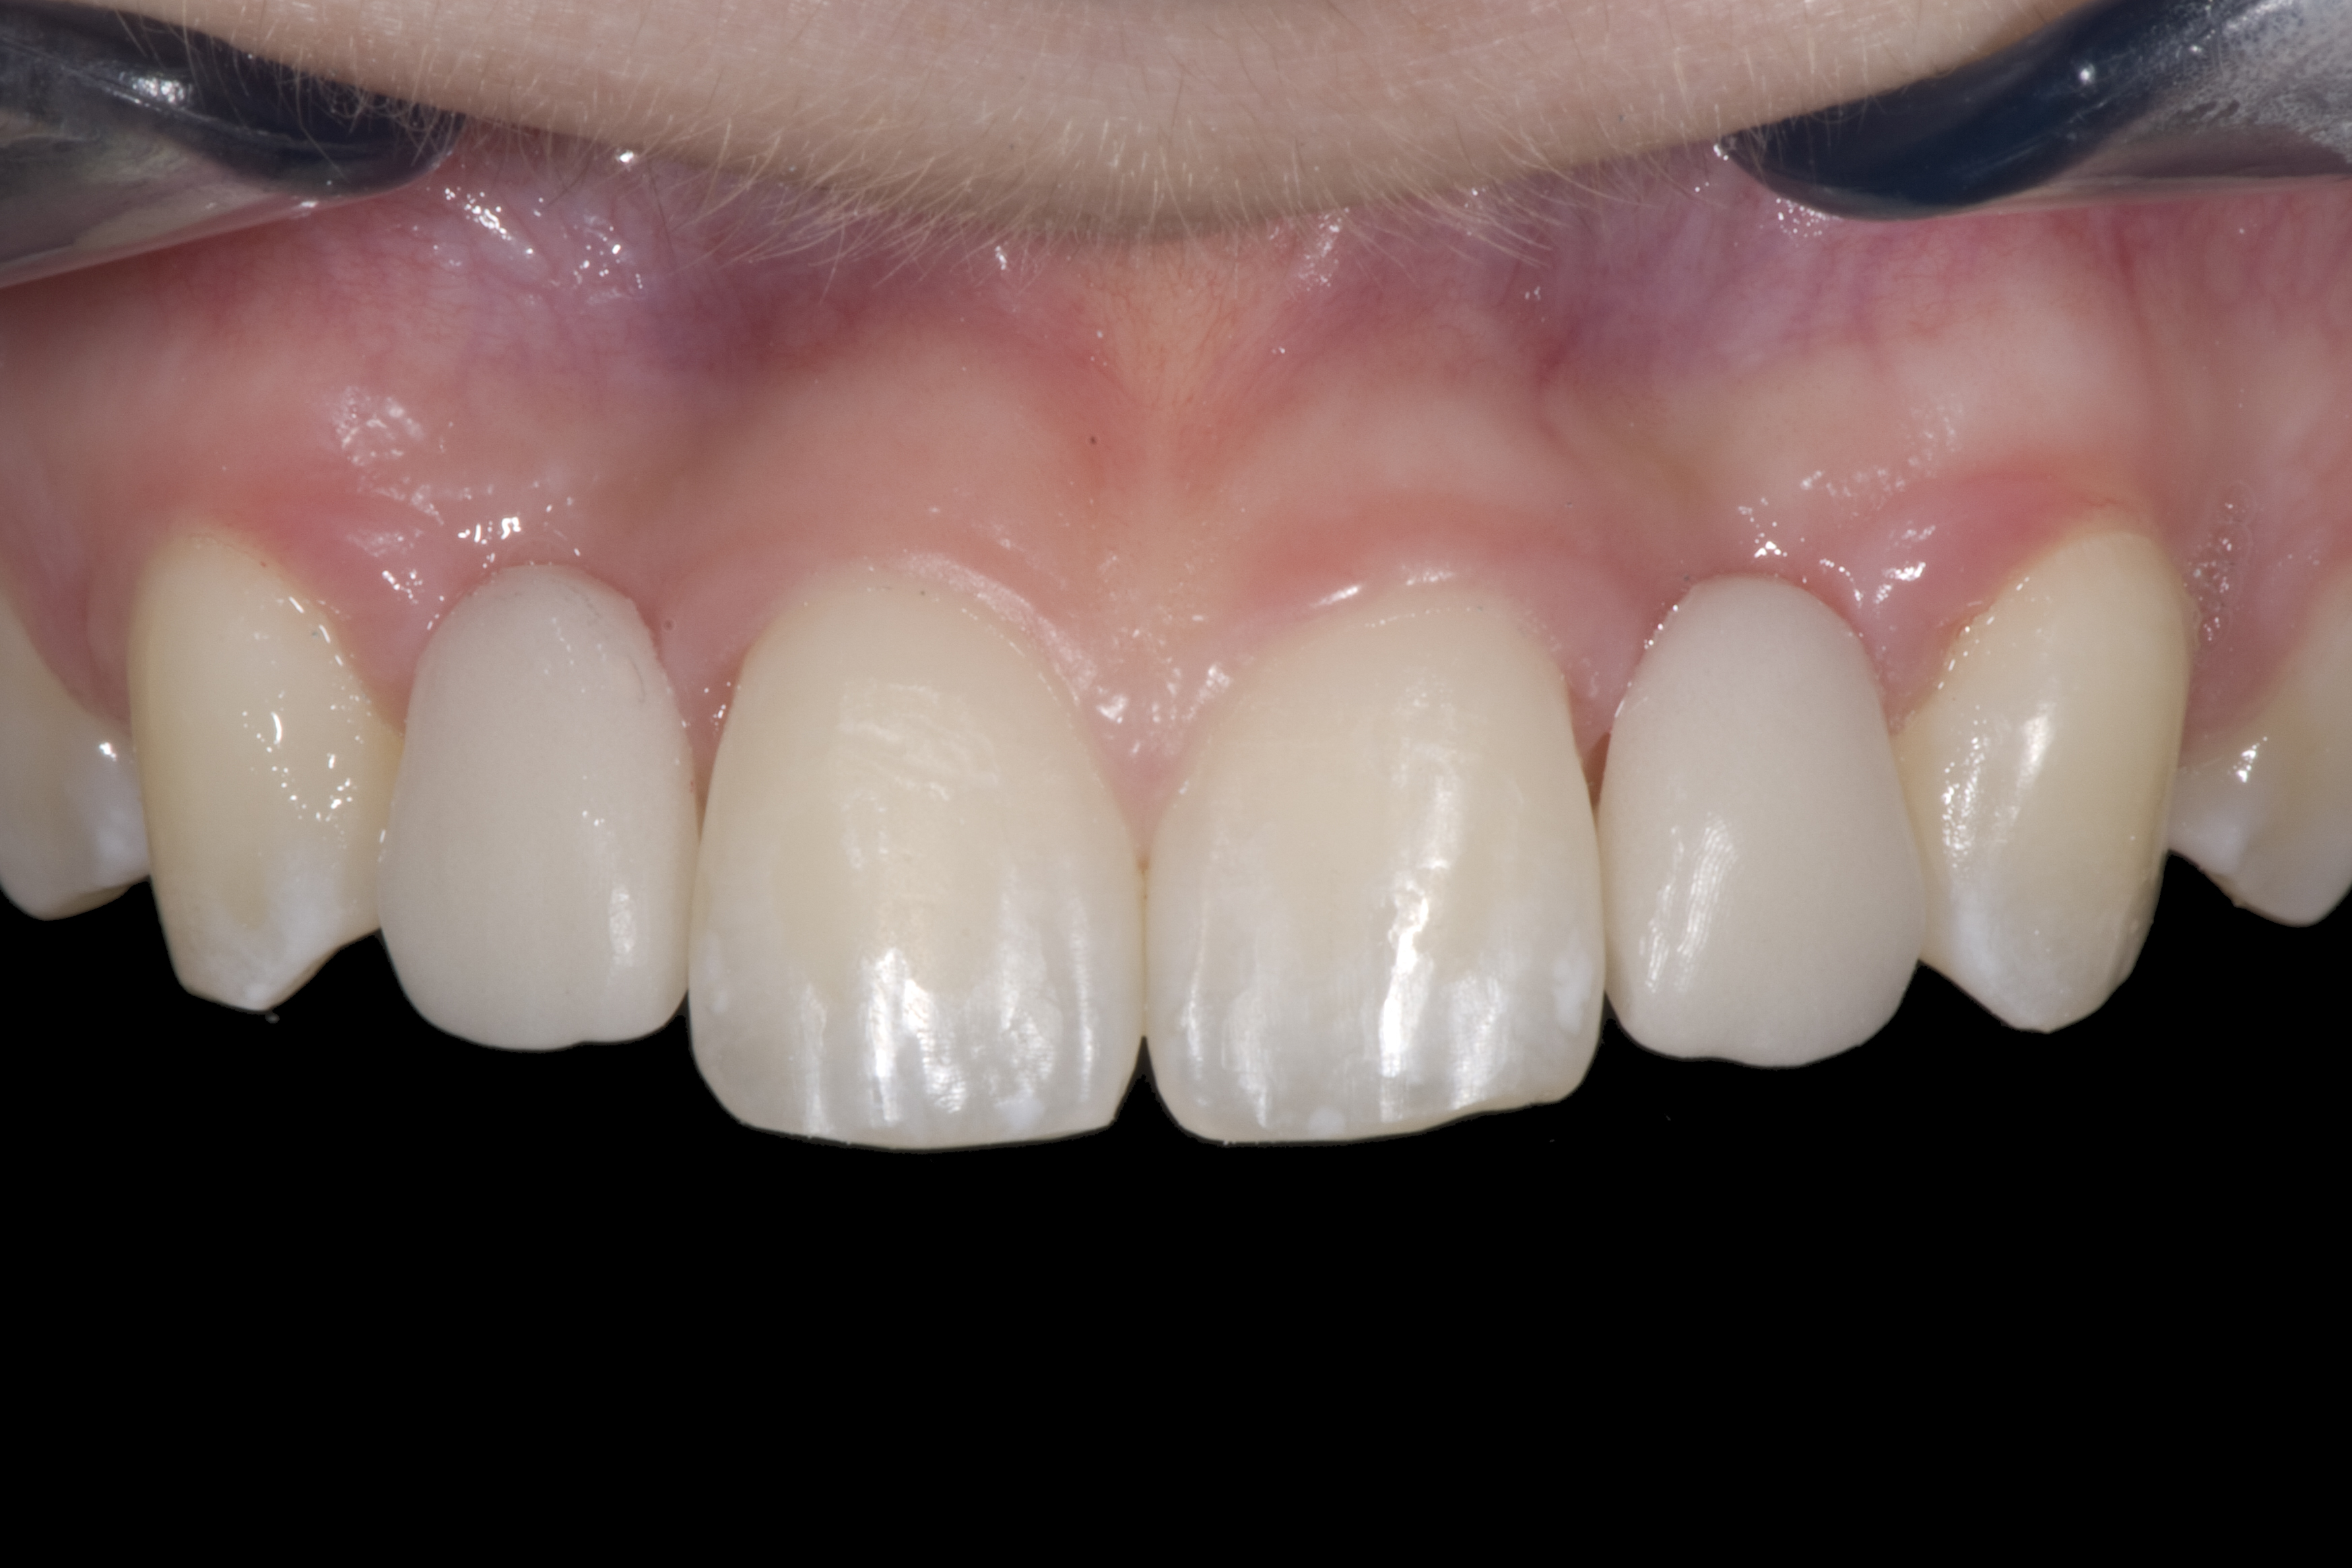

(12.) 15-year-old girl after orthodontic therapy idealized maxillary lateral incisor spaces.

Figure 12

(13.) Deficient ridges in the areas of the missing lateral incisors.

Figure 13

(14.) Occlusal view. Some form of augmentation would be needed if implants were being considered.

Figure 14

Some patients do not want an implant due to the need for surgical intervention, and others may not have enough space for implant placement. A 15-year-old patient presented to the office after completion of orthodontic treatment to idealize the spacing of her teeth and improve her occlusal relationship (Figure 12 through Figure 14). Because both of her maxillary lateral incisors were missing, the patient was wearing a retainer with lateral incisor pontics. She had a busy school schedule, but expressed her desire for a fixed restorative option. All of her options were discussed, and the patient was informed that if she wanted an implant, she would have to wait for at least 3 to 4 years for completion of growth. The patient was not sure if or when she wanted to have an implant placed in the future, especially considering her busy schedule and desire to attend college after high school. Considering her age and the need to be conservative, a single-wing zirconia Maryland Bridge was chosen as the ideal prosthetic replacement option. Because bonding a non-etchable and smooth surface such as zirconia requires chemical adhesion, it was decided to use a modified technique to make the bridge more retentive. One of the ways to improve adhesion of a zirconia bridge is to use an etchable feldspathic ceramic layer on the internal surface of the zirconia retainer.56-58 Unfortunately, it can be difficult to determine the thickness of the ceramic and ensure accurate seating of the restoration.

When the patient returned, the fit was evaluated in the mouth. Once verified, the internal surface of the framework was etched with a 9.5% hydrofluoric acid for 90 seconds and then salinized. After etching the enamel surface with phosphoric acid for 30 seconds and applying the primer (Single Bond Plus, 3M ESPE) to both the internal surface of the framework and the enamel, the zirconia bridge was bonded with a dual-cure resin cement (RelyX™ ARC, 3M ESPE). After the procedure, the patient ended up with a long-term, high-strength esthetic restoration advantaged by the bonding potential of fledspathic ceramic (Figure 20 through Figure 24). Six years after placement, the prosthesis had remained in place with no complications.